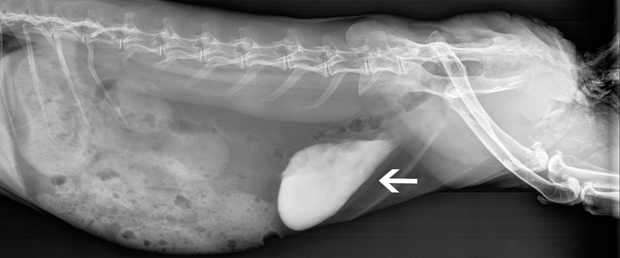

The arrow points to excess amounts of sludge (calcium) in a rabbit’s urinary bladder.

Treating rabbits with this problem involves lots of fluids, potassium citrate to bind the calcium, and reducing dietary intake of calcium. Therapy may even include the handle end of an electric toothbrush to massage the abdomen and help break up the calcium oxalate sludge so it can be urinated out.